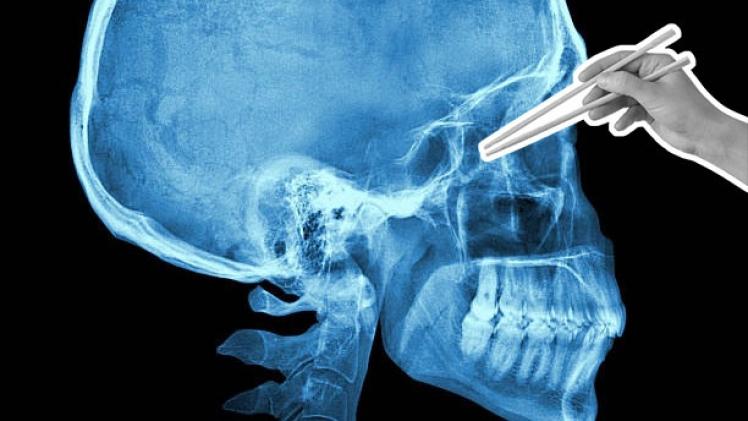

عندما سُئل الرجل عن حالته، لم يكشف عن أي سبب محتمل لهذه الأعراض، لكن الأشعة المقطعية أظهرت جسمان غريبان داخل الجمجمة، يبرزان من أنفه إلى دماغه. وبعد الفحص الدقيق، تم التعرف على الجسمين على أنها عيدان تناول الطعام مكسورة.

عند سؤاله عن كيفية وصول عيدان تناول الطعام إلى جمجمته، كان المريض البالغ من العمر 35 عامًا في البداية في حيرة من أمره مثل أطبائه، لكنه تذكر لاحقًا حادثة كان متورطًا فيها قبل خمسة أشهر والتي يمكن أن تساعد في تفسير وضعه.

فأثناء خروجه في إحدى الليالي، دخل الرجل في مشاجرة وانتهى به الأمر في غرفة الطوارئ. ويعتقد أن الرجل الآخر أدخل عيدان تناول الطعام في جمجمته، من خلال الأنف، لكنه لا يتذكر ما حدث بالفعل، حسب موقع "أوديتي سينترال".

وبعد دراسة جميع الخيارات، قرر الفريق الطبي إجراء عملية جراحية بالمنظار من خلال الأنف، إلى جانب الجراحة المجهرية لإغلاق الناسور القحفي للمريض وإزالة زوج عيدان تناول الطعام المكسورة.